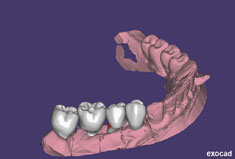

Fehlen in der Front oder im Seitenzahnbereich mehrere Zähne, ist eine Brücke oder Prothese vollkommen unnötig. Die fehlenden Zähne können entweder einzeln durch eine entsprechende Anzahl von Implantaten oder durch implantatgetragene festsitzende Brücken ersetzt werden. Das Bild der Kronen zeigt die drei Verschraubungen deutlich, im Mund liegen diese verdeckt am Gaumen oder im Bereich der Zunge.

DVT mit 3D-Planung